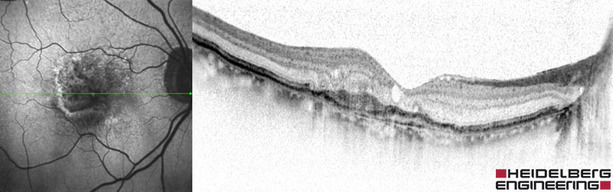

Current photographic technology allows us to see the surface of your retina (a bit like looking at the cover of a book) and identify substantial changes to the surface often showing too little information, too late. 4D eye scans allow us to see the individual cells in your retina (like reading every letter in a book) and so can identify tiny changes much earlier. But imagine if we could not only see the tiny cells at the back of your eye but also what these cells contained and, therefore, analyse how efficiently they were working thus predicting where damage may occur and treat conditions before they cause sight loss. Imagine if we could do this with just the use of light, do it non-invasively and comfortably. Well, thanks to Blue Peak technology this is now possible.

If your optometrist detects any change or is concerned about your family history, they may suggest taking further measurements of your macula for future comparison. These include 4D OCT scans and multi- colour images.